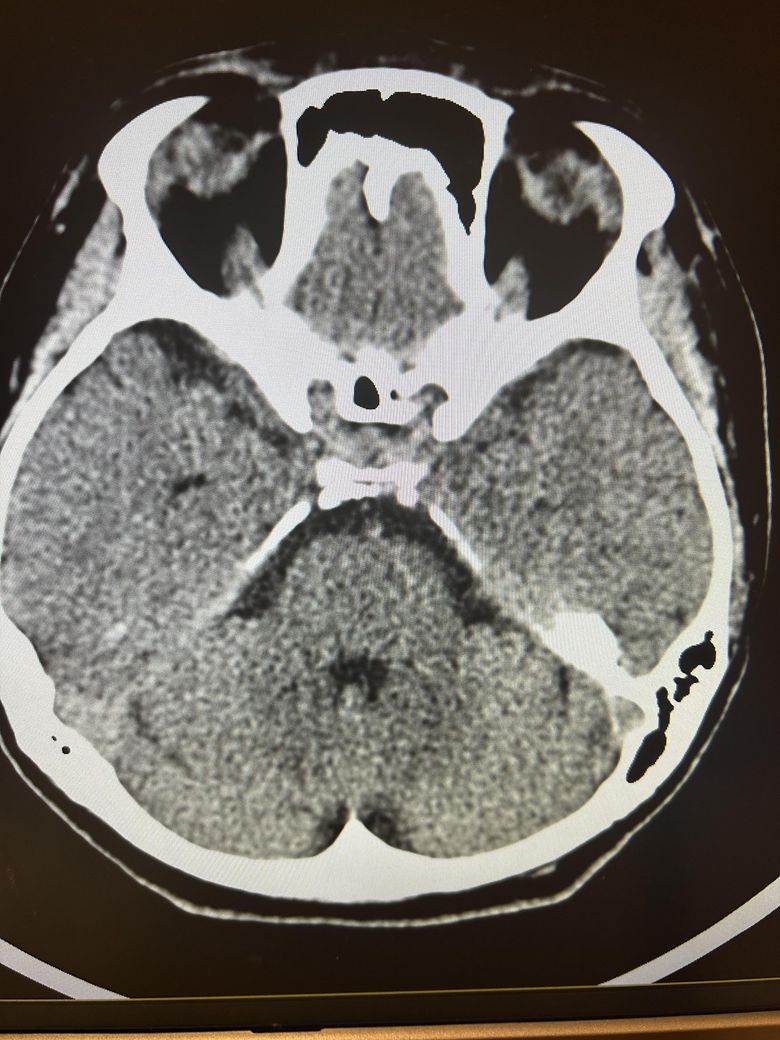

두통과 목뻐근함이 일주일째 심해서 뇌ct검사를 했습니다.

영상은 이렇게 보이는데 어떻게 의심되시나요?

석회화랑 다른것도 보이시나요?